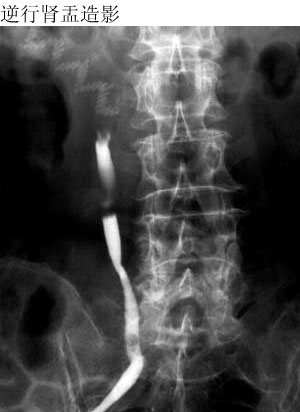

CT00401: (K) [原创]右肾病变(近期手术)。 ...

CT00401: (K) [原创]右肾病变(近期手术)。

女性患者65岁。无痛血尿一个月。 您的诊断?依据?右上段输尿管如何解释?请赐教!

1、逆行输尿管造影见上段梗阻,断端呈杯状。

2、ct扫描见上段输尿管增粗。

3、肾积水,为阻塞性,因尿液浓缩ct值偏高,伴肾萎缩,形态较对侧小。

4、可伴有下段或膀胱的多发肿瘤(或癌、或息肉、结石),逆行输尿管造影见其下段有充盈缺损。

5、高发年龄为60岁左右,临床有无痛性血尿。